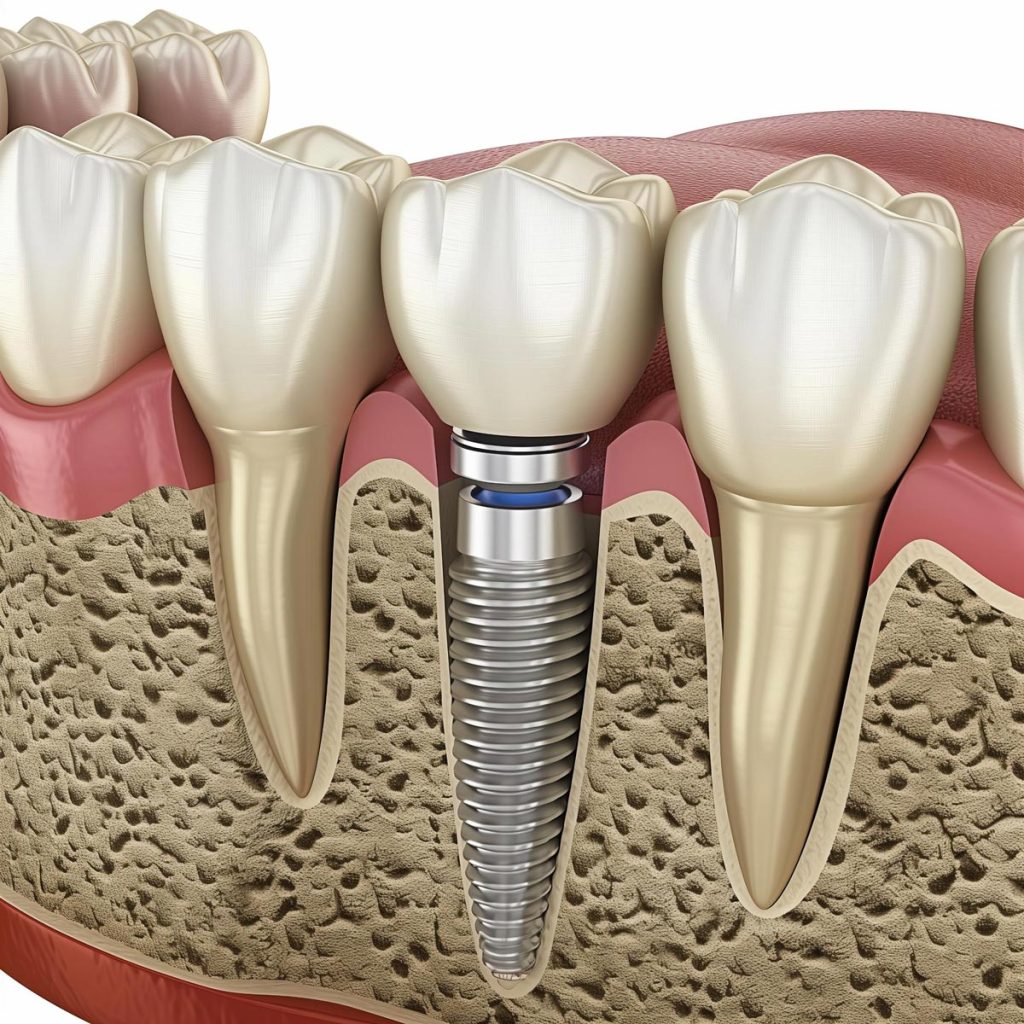

While many people visualize the finished product of dental implants (crown and all), a dental implant is essentially an artificial tooth root. It’s made from titanium or a similar biocompatible material and placed directly into your jawbone where a natural tooth used to be. After this implant heals, it’s then capped with a crown or other dental device.

A complete dental implant actually has three main parts:

- The implant post, which takes over as the root of your new tooth

- The abutment, which is how the implant post connects to your crown

- The crown, which is the custom-made, tooth-colored cap that looks like your natural teeth

Together, these components mimic your natural tooth’s structure and result in a dental replacement that feels strong, stable, and permanent.

The magic behind dental implants is a process called osseointegration. It’s what happens when your implants are placed in your jawbone, and the bone heals around them, fusing the anchor firmly.

The implants we use at Erik’s Dental Group are medical-grade titanium or zirconium, which have a special ability to integrate with living bone tissue without causing rejection or irritation. Over a period of several months, your jawbone heals around the implant, and at this point, it’s often stronger than the original tooth root it replaced.